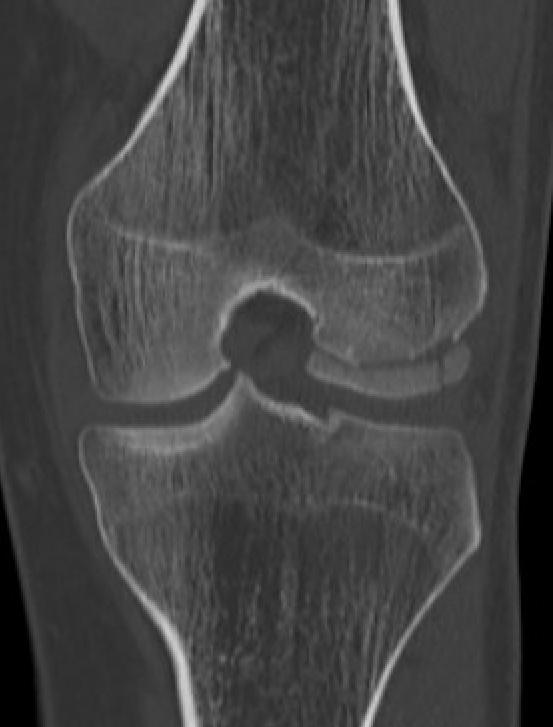

CT

Osteochondral fracture of the lateral femoral condyle

Large osteochondral fracture medial facet patella

Large osteochondral fracture lateral femoral condyle